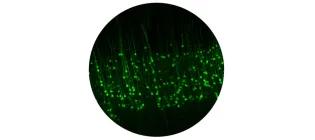

Two astrocytes in green enwrapping brain blood vessels in magenta.

UK DRI Programme Leader (Fellow)

We investigate the contribution to brain function and dementia made by communication of brain support cells called astrocytes with the vasculature.

B.Diaz-Castro@ed.ac.uk

Image credit: Carlos Parra-Pérez